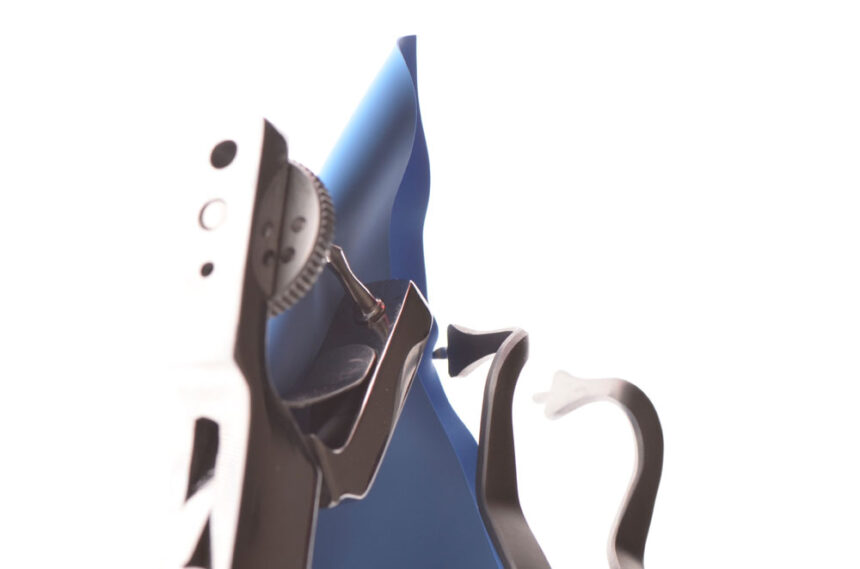

Στην εποχή της συγκολλούμενης αποκαταστατικής οδοντιατρικής ο έλεγχος της υγρασίας στο πεδίο εργασίας αποτελεί σημαντικό παράγοντα στην επιτυχία της τελικής θεραπείας. Ο οδοντίατρος καλείται να εκτελέσει σύγχρονα πρωτόκολλα διατηρώντας περισσότερη οδοντική ουσία και δημιουργώντας αποκαταστάσεις με μεγαλύτερη μακροβιότητα.

Στο σεμινάριο αυτό θα γίνει ανάλυση όλων των προτεινόμενων τεχνικών για την εφαρμογή της ελαστικής απομόνωσης σε άμεσες θεραπείες, σε συγκόλληση έμμεσων αποκαταστάσεων, σε συνθήκες επαναπροσδιορισμού του αυχενικού ορίου, στην εφαρμογή της σε περιστατικά ενδοδοντικών διαδικασιών., καθώς και στη χρήση αυτής σε ψηφιακή αποτύπωση. Αφού αναλυθεί ο κύριος εξοπλισμός και παρουσιαστούν οι αντίστοιχες προσεγγίσεις, ιδιαίτερη σημασία θα δοθεί στο πρακτικό μέρος της εξάσκησης των συμμετεχόντων σε σενάρια που προκύπτουν στην καθημερινή κλινική πράξη.